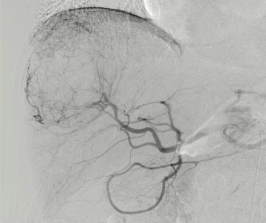

TACE经验:肝癌有N多的供血动脉 SIRT 也同样要求栓塞所有的供血动脉 需要分别超选择三支供血动脉 position 1 Position 2 Position 3

| 需要分别超选择三支供血动脉 |

| position 1 |

| Position 2 |

| Position 3 |